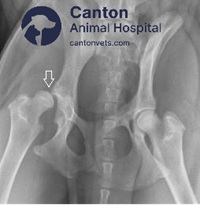

C. Femoral Head Ostectomy (FHO)

Best for: Small to medium-sized dogs with severe hip pain.

Procedure: Removes femoral head to create a false joint.

Outcome: Reduces pain; allows near-normal movement over time.

Femoral Head Ostectomy (FHO) Surgery in Dogs & Cats

What Is FHO Surgery?

Femoral Head Ostectomy (FHO) is a surgical procedure used to treat hip disorders by removing the femoral head (ball) of the hip joint, eliminating bone-on-bone contact and reducing pain. Over time, a false joint forms with surrounding muscles supporting movement.

FHO Surgery Procedure

Step 1: General anesthesia is administered Step 2: A small incision is made over the hip joint Step 3: The femoral head (ball) is surgically removed Step 4: Soft tissues and muscles help form a false joint Step 5: The incision is closed, and recovery begins